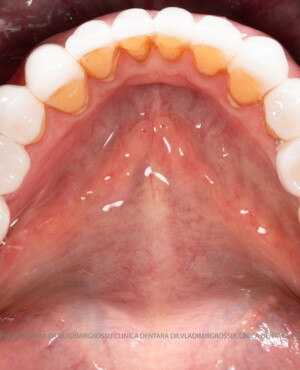

După extracția dentară, în intervalul de 6-12 luni, osul alveolar suferă un proces natural de remodelare, ceea ce conduce la scăderea volumului osos prin rezorbție. De aceea, inserția implantului dentar este ideală imediat după extracție sau, cel târziu, în primele 3-4 luni după aceasta.Scopul procedurilor de adiție osoasă este refacerea fundației osoase necesare pentru stabilizarea corectă a implantului dentar. Pentru ca un implant să reziste în timp la forțele masticatorii, este nevoie de o bază osoasă solidă și sănătoasă.

Adiția de gingie (gingivoplastia)

Aditia gingivală este o procedură chirurgicală ce corectează diverse probleme estetice și funcționale, cum ar fi recesiunea gingivală. În implantologia modernă, aditia de țesut moale este utilizată aproape în fiecare intervenție de inserție a implantului dentar pentru a asigura un aspect estetic natural și o bună integrare a implantului în cavitatea bucală.